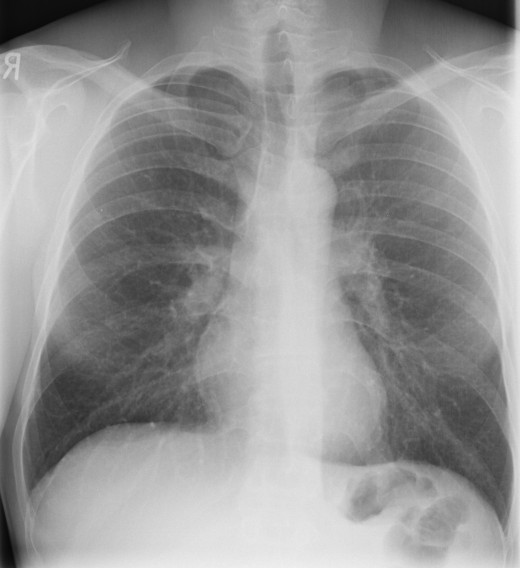

24. Mild pulmonary congestion. PA chest radiograph

Radiograph signs: Kerley A and B lines (interlobular-interalveolar septa in both hila or basal along the lateral chest wall); apicobasal caliber discrepancy (upper-zone redistribution of blood flow); confluent symmetrical, bibasal airspace shadows without air-bronchogram; principally the hilar regions are concerned (perihilar bat’s wing pattern); usually cardiomegally occurs.